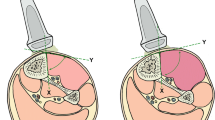

A beanbag was positioned underneath each pig to maintain the supine position throughout the experiment (Fig. 7). The tibialis anterior muscles of both hind limbs of the pig were selected as the target muscles. Both muscles were identified under ultrasound guidance and marked with a pen. Two ultrasound imaging machines, Aplio i700 (Canon Medical Systems, Tochigi, Japan) were used to quantify the shear modulus of elasticity of the tibialis anterior muscle in the SEG and to quantify the echogenicity and arterial blood flow velocity in the EG. In the SEG, the i18LX5 linear probe was used to collect SWE images of each hind limb at 15MHz. Each probe was placed longitudinally to the marked tibialis anterior muscle belly and angled 90° with the skin surface to maintain the same contact pressure and position throughout the experiment using the three-dimensional (3D) printed probe holder with an adjustable cell phone holder fixed on the experimental table (Fig. 7). In the EG, the PLT-1005BT linear probe was used to collect echogenicity data and arterial blood flow velocity of each hind limb at 11MHz with 82 gain, and each probe was placed transversely to the marked tibialis anterior muscle belly with the other experimental conditions similar to the SEG (Fig. 7). A 24-gauge heparinized IV catheter (Jelco® IV catheter radiopaque, Smith Medical, Ashford, UK) was inserted into the carotid artery to measure the systolic and diastolic central blood pressure. It was connected to a pressure-transducing device (AMK 150®, Ace Medical Co., Seoul, South Korea) and continuously monitored each pig’s condition throughout the experiment using a patient monitor (BM5, Bionet Co. Berlin, Germany). A 16-gauge heparinized IV catheter (Jelco® IV catheter radiopaque, Smith Medical, Ashford, UK) was gently inserted in the intermuscular plane between the tibialis anterior and peroneus muscles under ultrasound guidance to measure the ICP of the anterior compartment of the porcine leg, which was also connected to a pressure-transducing device and continuously monitored.

A surgical procedure to induce the compartment syndrome

Each pig was placed on a surgical table in a supine position. The position was maintained by a beanbag laid beneath the pigs’ back and buttocks, and both hind limbs were restrained by an elastic band in a fully extended position. A 15 cm skin incision was made along the inguinal line in the left hind limb. After subcutaneous dissection, the vascular bundle containing the femoral artery and vein was detected at the intermuscular plane of the medial thigh. Sharp dissection was performed proximally along the femoral artery after incision of the thick inguinal ligament. In the retropelvic space, the common iliac artery (CIA) was observed and tied with a rubber sling to block the blood flow of the CIA. The proximal thigh was tied with an elastic band to block other innominate collateral arteries around the thigh. The tension of the elastic band was adjusted to block all the arterial flow, and the complete blockage of blood flow to the left hind limb was confirmed using Doppler ultrasonography. Previous studies revealed that CS was induced by reperfusion after 6 h of leg ischemia48,49. Thereby, we used 6 h for the injury time using leg ischemia. No surgical procedure was performed in the right hind limb since it was considered the control condition.